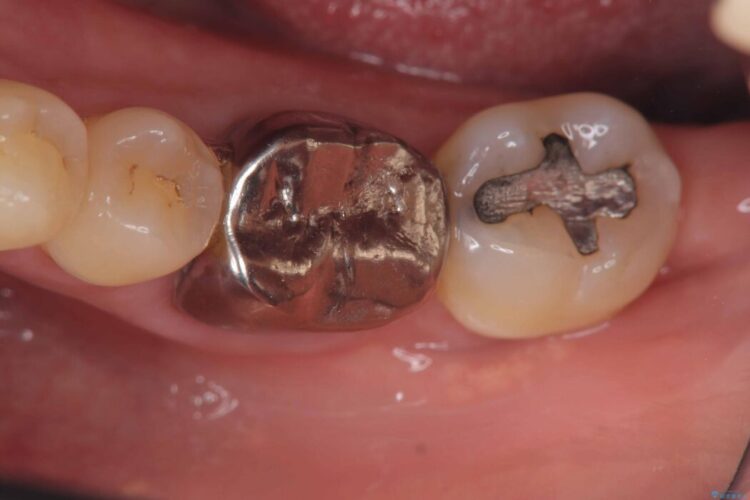

破折したセラミックインレーのやり替え

他院で装着されたセラミックインレー(MOD窩洞)が破折したとご来院されました。

治療期間(治療回数):1ヶ月(2~5回) | 概算治療費:15.4万円(税込)(オールセラミッククラウン14.3万円+仮歯1.1万円)